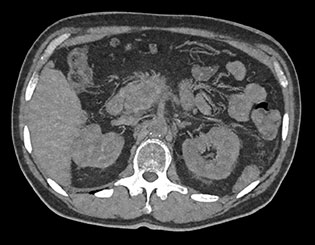

Obraz MonoE

Na tym zdjęciu pokazano zsyntetyzowany obraz monoenergetyczny uzyskany przy wstępnie ustawionej wartości keV.

MonoE